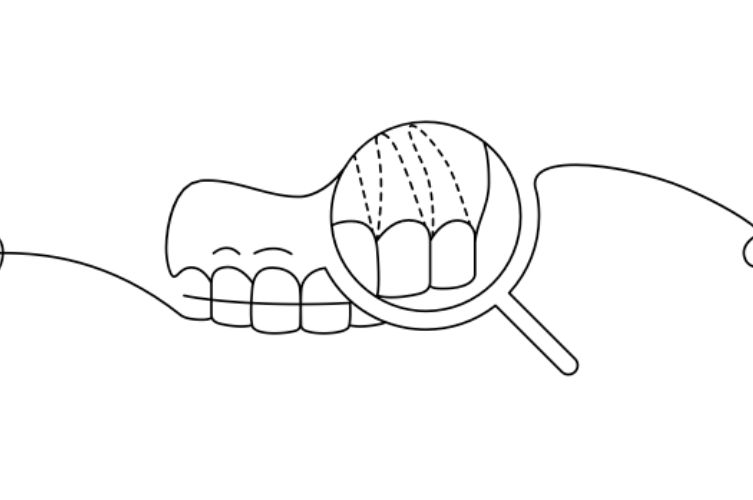

Les aligneurs invisibles sont conçus pour offrir la plus grande transparence et respecter l’esthétique naturelle des dents. Il n’affecte pas l’esthétique des patients pendant le traitement.

Le traitement consiste à appliquer, pendant une durée prédéterminée, une série d’aligneurs fabriqués à partir d’un composé thermoplastique de pointe qui adhère à la surface des dents. Les aligneurs sont créés après numérisation et analyse numérique des arcades dentaires, ce qui permet de visualiser immédiatement le résultat final et la durée du traitement. Le traitement est donc réalisé sur mesure par le Docteur Ludovica MARTINI.